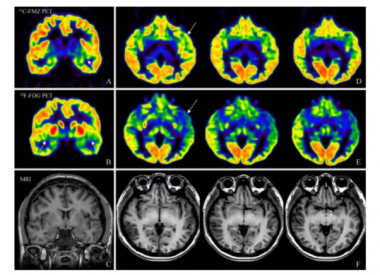

MRI兼容的高性能PET研究及医学应用——中国科学院深圳先进技术研究院研究员柳正